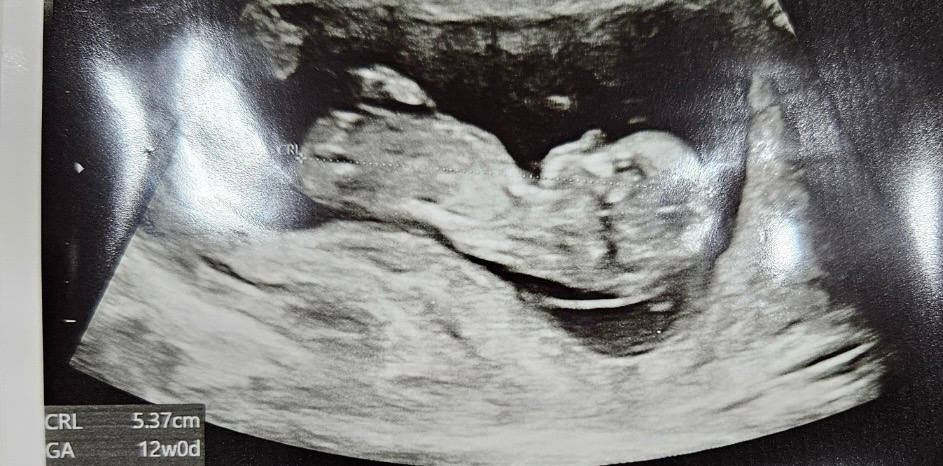

각도법 고수님들 한번 봐주실 수 있나요?😃

각도법으로 알아 볼 수 있을까요??ㅎㅎㅎ

잘은모르지만 각도법 요즘 열심히 공부하는중이었어서 조심스레 공주님에 한표요..😛